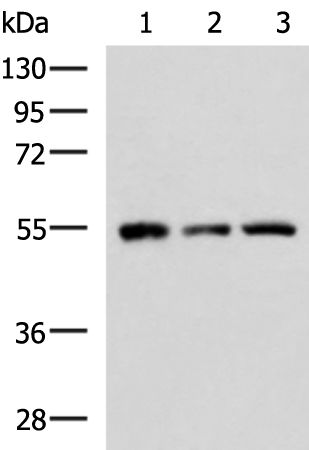

分类: 科研抗体货号: P04091别名: MEK2, MKK2, MAPKK2, PRKMK2应用: WB,IHC反应种属: Human, Mouse, Rat